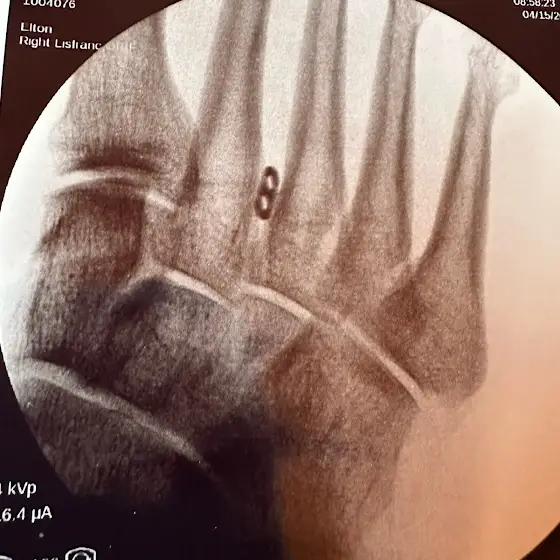

The surgery went well. I have a small metal plate reconnecting my lisfranc ligament. Now to manage the pain and heal up. Much love 💕